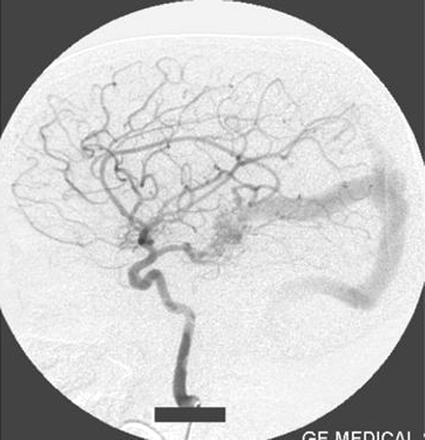

The second case is a girl (1 year 2 months of age) who presented with a history of rapidly enlarging head size and a prominence of veins on the forehead. Angiography showed a left proatlantal artery of external carotid artery origin associated with a mural-type of Galen’s vein malformation that was supplied by the left anterior choroidal artery and thalamoperforators of the left posterior cerebral artery. The venous drainage was to the transverse sinus with some retrograde flow to the superior sagittal sinus. The origin and course of the proatlantal artery were the same as in case 1, and the occipital artery took its origin from the proatlantal artery (Fig 10).

Right common carotid artery injection angiogram shows the origin of the proatlantal artery and the filling of the vertebral artery (case 2).